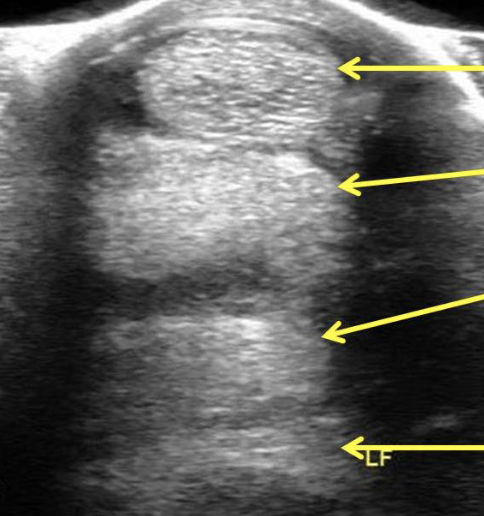

label equine distal limb ultrasound (top to bottom)

superficial digital flexor

deep digital flexor

check ligament

suspensory ligament

what is this

superficial digital flexor tendonitis

black round object on imaging= hematoma

what is this

left= normal

right= deep digital flexor tendonitis

yellow arrows= tear in deep digitial flexor tendon

what is this

left= normal

right= suspensory ligament desmitis

cloudyness (red arrow) is showing fluid injury

white lines on left image is normal for comparison

what is this

suspensory ligament desmitis

green is surrounding tear

on left side of MRI, bulging out is visible, hitting neurovascular bundle and causing pain